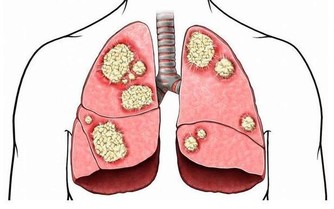

從中醫的角度上來講,入脾,肺兩經,能夠幫助調理營養不良,燥咳少痰,食少體弱,產婦乳少,皮膚紫斑,咯血,大便燥結等等。